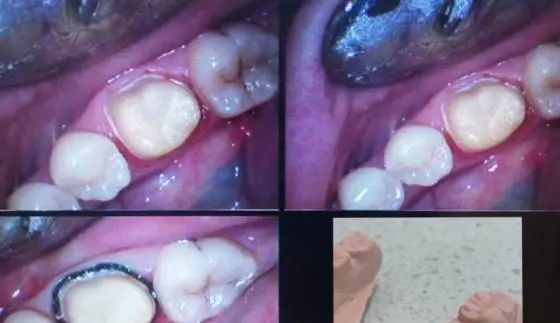

口内效果,舌侧由于牙周出血,肩台不清晰